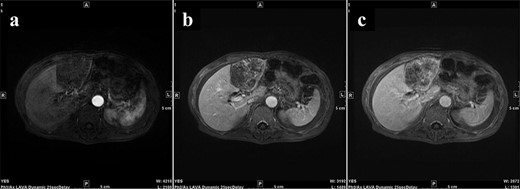

A 77-year-old man was referred to the Department of Gastroenterology at our hospital for suspicion of hepatocellular carcinoma and cancerous peritonitis. He was scheduled to be hospitalized for a thorough examination at a later date. However, 3 days after his first visit, he returned to the Emergency Department with a complaint of abdominal distension. He was hospitalized on the same day with a diagnosis of intra-abdominal bleeding due to a ruptured tumor in the lateral section of the liver. Computed tomography (CT) and magnetic resonance imaging (MRI) revealed a tumor with a maximum diameter of 8 cm in the lateral hepatic region and ascites around the liver and in the pelvic floor. Dynamic CT showed blood vessel-like early staining inside the tumor, and the contrast effect gradually enhanced (Fig. 1). During gadolinium ethoxybenzyl diethylenetriamine pentaacetic acid-enhanced MRI, this contrast effect gradually increased from the peripheral part toward the hepatocyte phase from the arterial phase (Fig. 2). Levels of tumor markers (alpha-fetoprotein, protein induced by vitamin K absence or antagonist-II, carcinoembryonic antigen and carbohydrate antigen 19–9) were within the normal range (Table 1). Based on the imaging findings, a diagnosis of spontaneously ruptured hepatic hemangioma was made. Since the patient’s general condition was stable and there were no findings suggestive of active bleeding, he decided to undergo elective surgery. Thus, he was not requested to continue being hospitalized and was discharged. Six days after discharge, he was transported to the emergency room in a state of shock and was hospitalized the same day. With the diagnosis of hemorrhagic shock due to re-rupture of the liver tumor (Fig. 3), emergency transarterial embolization (TAE) was performed. No apparent extravasation was observed on angiography, and A3 was embolized. Seven days later, he underwent left lateral hepatic segmentectomy. The postoperative course was generally good. The post-ruptured tumor was found in the left lateral segment, the cut surface was white, the edges were brown and the boundaries were unclear (Fig. 4). Histopathological examination revealed that sections of the white and brown parts of the margin were viable tumors, showing highly atypical spindle-shaped cells, arranged like sinusoidal vessels and partly solid, and there were many mitotic figures. There was no capsule, and the tumor infiltrated the surrounding liver parenchyma (Fig. 5a–c). Immunostaining showed CD31 (+), CD34 (partially positive), CK-CAM5.2 (−), α-SMA (−), HMB45 (indeterminate) and p53 (+), and the patient was diagnosed with hepatic angiosarcoma (Fig. 5d). Fever was observed 21 days after surgery, and CT was performed, revealing multiple masses in the liver (Fig. 6a). Another CT scan was performed 27 days postoperatively, which suggested that the liver masses were rapidly increasing; hepatic angiosarcoma recurrence was then confirmed (Fig. 6b). The patient requested the best supportive care at home and was discharged 31 days after the operation. He died at home 36 days after surgery.

During Gd-EOB-DTPA-enhanced MRI at the time of initial hospitalization, the contrast effect of the tumor gradually increased from the peripheral part toward the hepatocyte phase from the arterial phase. (a) Arterial phase, (b) portal phase, (c) hepatocyte phase. Gd-EOB-DTPA, gadolinium ethoxybenzyl diethylenetriamine pentaacetic acid; MRI, magnetic resonance imaging.